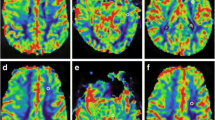

For each trial, each reader obtained overall significantly different nrCBV (P <. 001) and nADC (P < .001) values between the four normalization methods (Figs. 2 and S1). In post-hoc analyses, there were significant differences in nrCBV and nADC between CSO and TUM normalization methods (Table S1; Figs. 2 and S1). For example, when comparing CSO and TUM methods in trial 1, the median difference in nrCBV and mean difference in nADC ranged in magnitude between 0.10–0.27 and 0.07–0.09, respectively (Table S1). However, there were no significant differences in nrCBV or nADC between planar and spherical methods within the same normalization region (CSOp vs. CSOs or TUMp vs. TUMs). For these comparisons, the median difference in nrCBV and mean difference in nADC in trial 1 was greatly reduced to magnitudes ranging between 0.02–0.05 and 0.002–0.001, respectively (Table S1). ICC analyses indicated that each normalization method had excellent reproducibility (r > 0.90 as stated by Koo et al. [37]) between readers (Table 2; Fig. S2) and within readers when they repeated NAWM segmentations after 1 month (Table 2; Fig. S3). As a validation step, ROC curve analyses for IDH-mutation status prediction revealed that the nrCBV and nADC values yielded similar area under the curve values regardless of normalization method (Figs. 3 & S4; trial 1 AUC for nrCBV = 0.73–0.80; AUC for nADC = 0.88–0.91).

Differences in nrCBV and nADC based on normalization method (trial 1). Post-hoc analyses revealed significant differences for A/B nrCBV and C/D nADC between centrum semiovale (CSO) and tumor slice (TUM) methods for both readers in trial 1, but not between planar (p) and spherical (s) methods within the same normalization region. △ indicates median; * indicates P < .05; ** indicates P < .01; *** indicates P < .001. nrCBV, normalized relative cerebral blood volume; nADC, normalized apparent diffusion coefficient